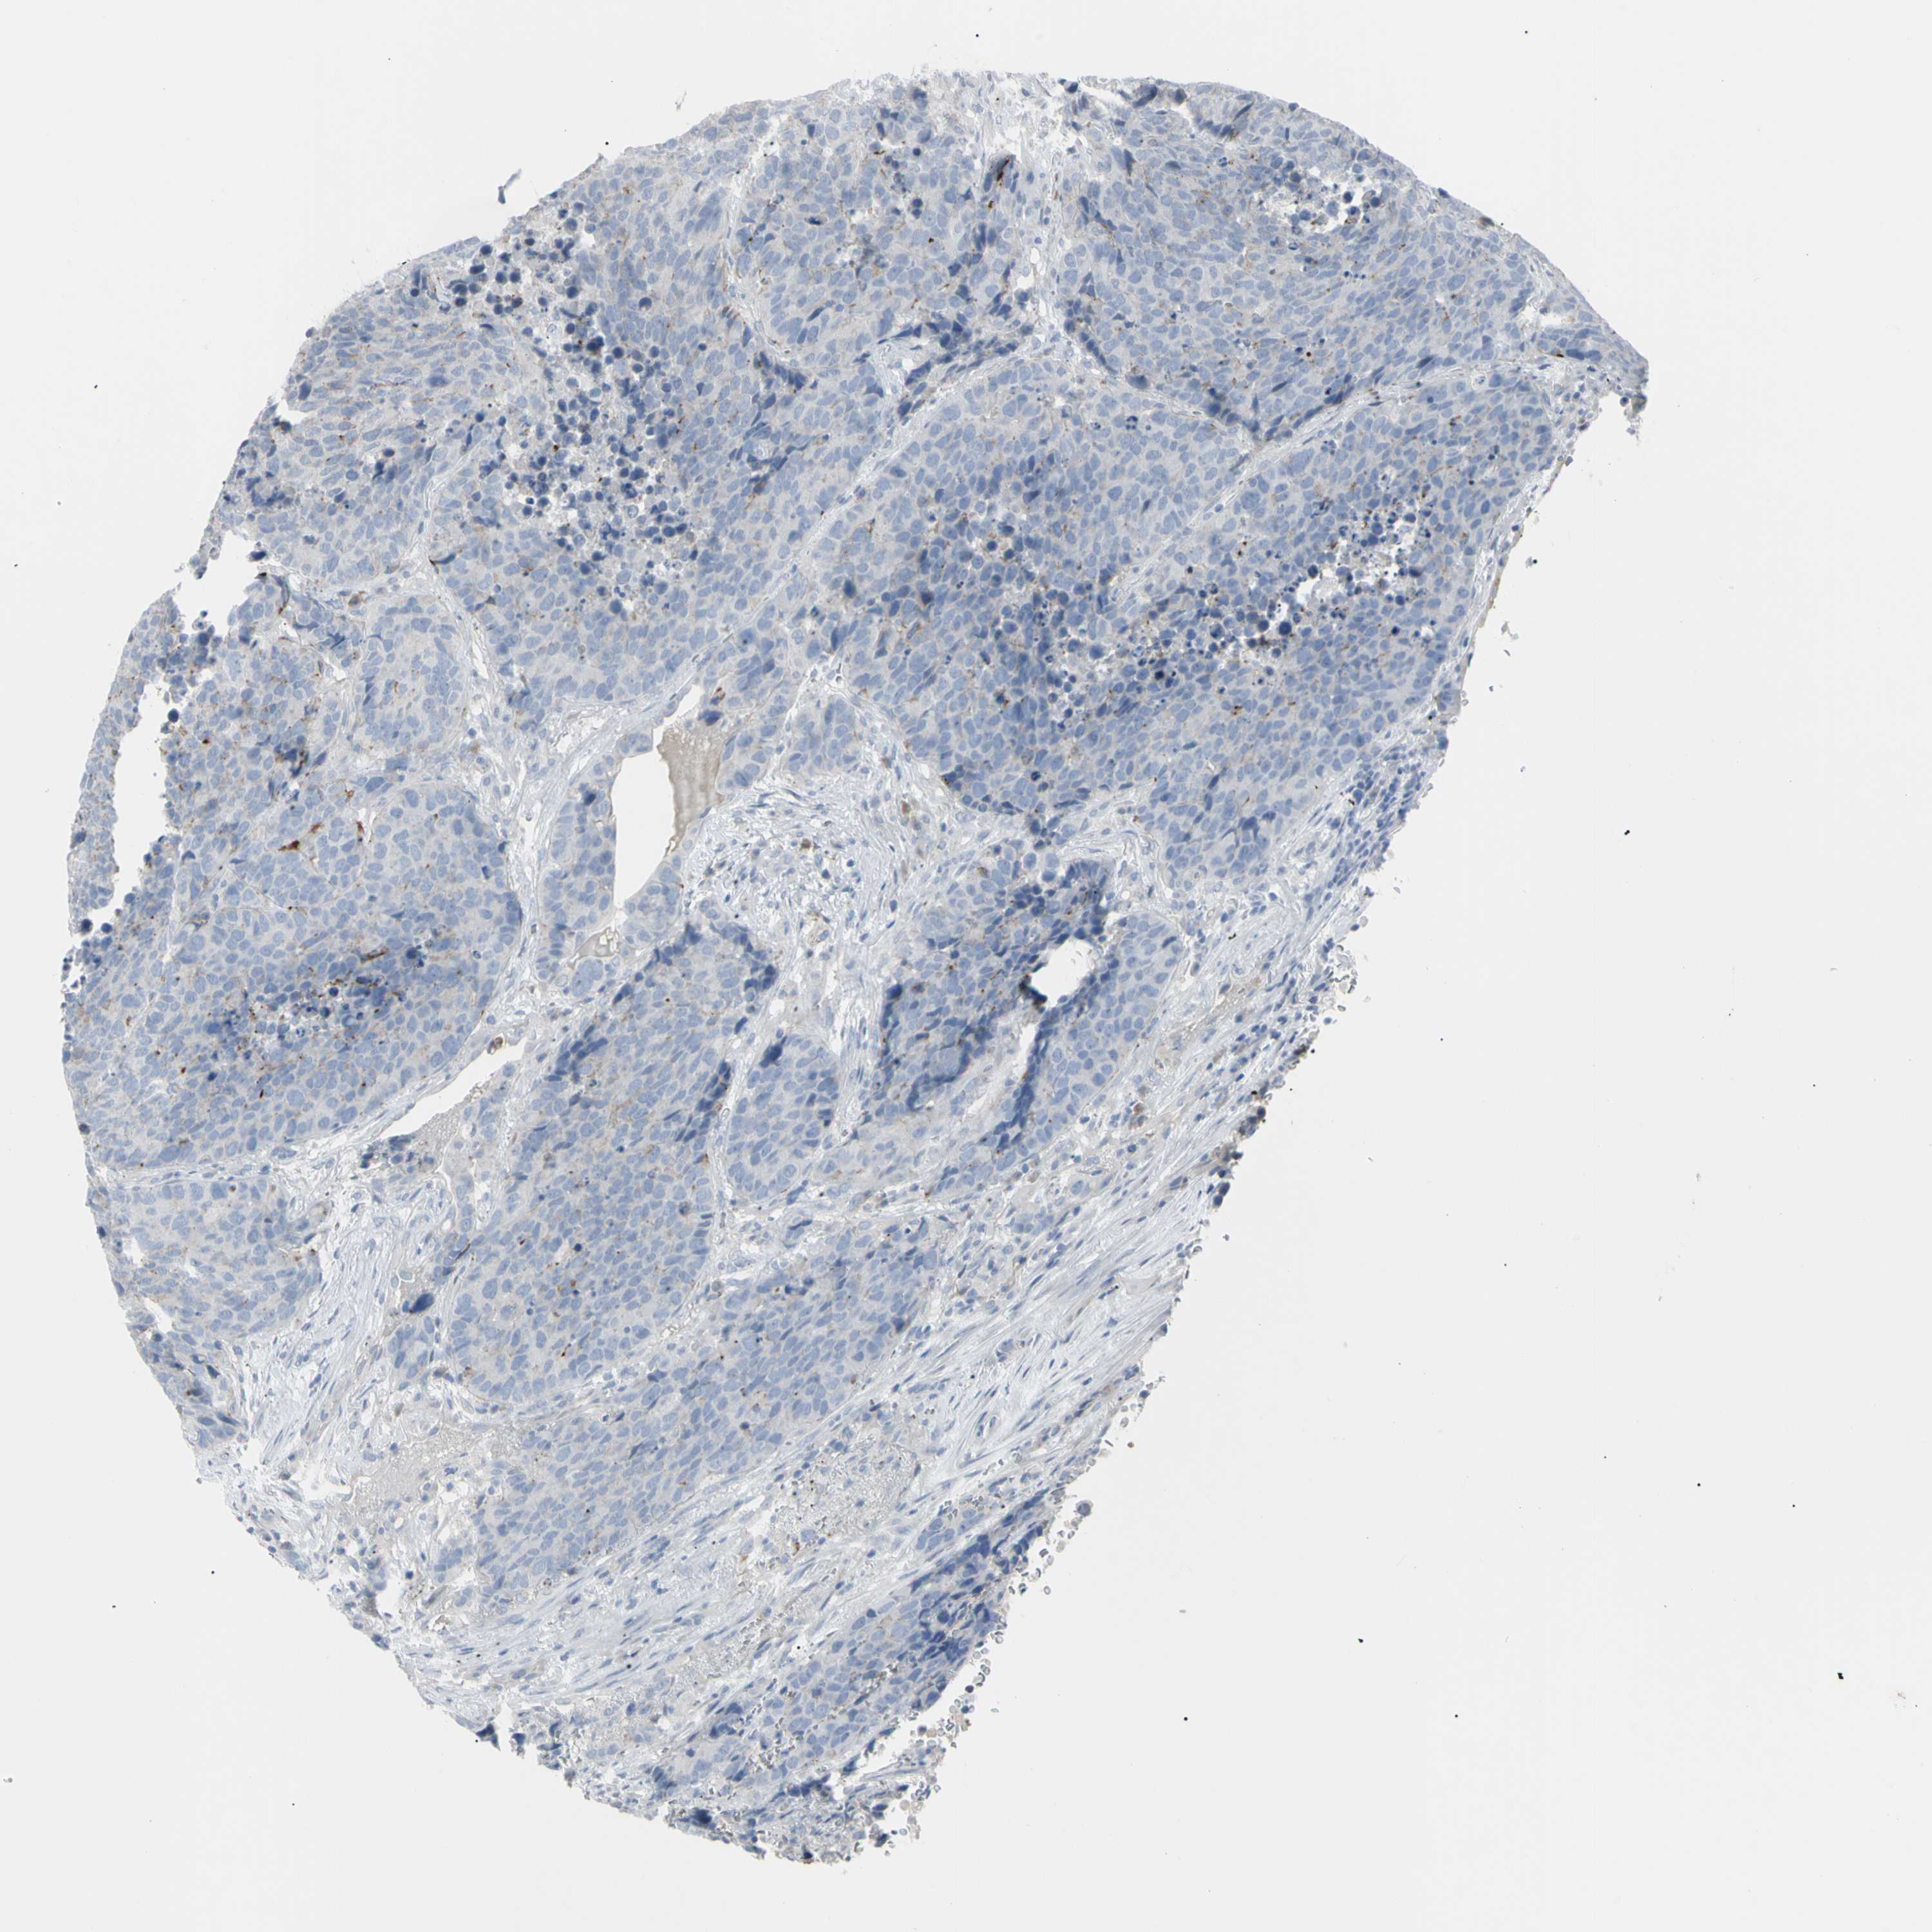

CARCINOID - Protein expressioni

A mouse-over function shows sample information and annotation data. Click on an image to view it in a full screen mode. Samples can be filtered based on level of antibody staining by selecting one or several of the following categories: high, medium, low and not detected. The assay and annotation is described here.

Antibody staining in the annotated cell types in the current human tissue is reported as not detected, low, medium, or high, based on conventional immunohistochemistry profiling in selected tissues. This score is based on the combination of the staining intensity and fraction of stained cells.

Each image is clickable and will lead to virtual microscopy that enables deeper exploration of all samples and also displays staining intensity scores, fraction scores and subcellular localization as well as patient and tissue information for each sample.

Antibody HPA009177

Carcinoid, malignant, NOS